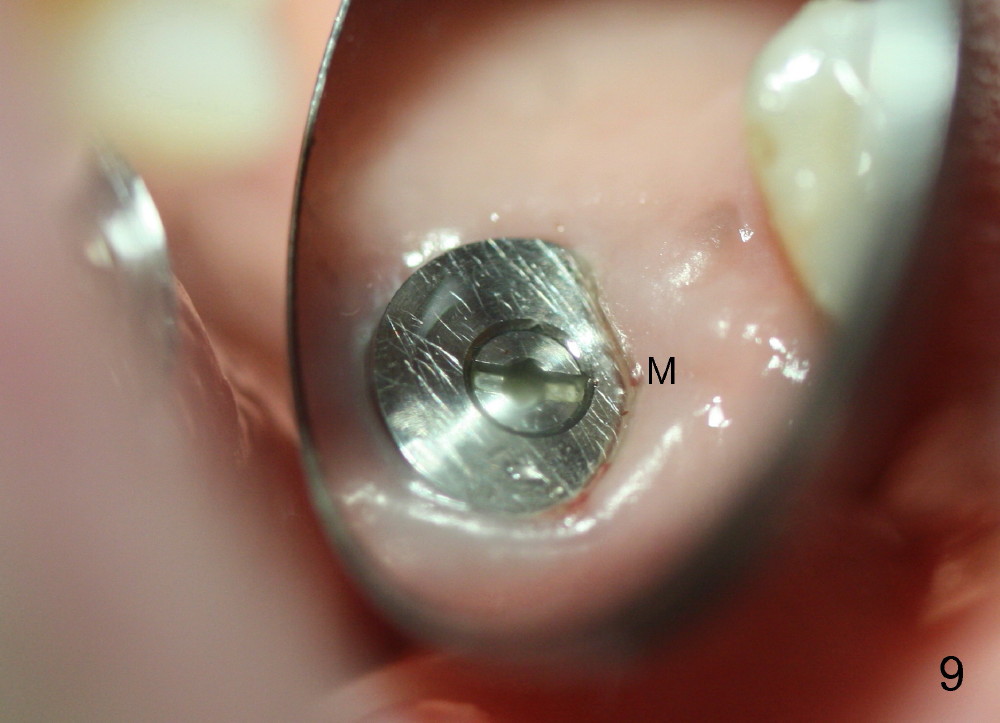

The upper right 1st molar fractures, the lingual portion mobile (Fig.1). There are deep pockets mesiolingually and distolingually. Fig.2 is preop PA, showing mesial bone resorption (*). The 84-year-old lady agrees extraction and immediate implant. Extraction is difficult due to not only root fracture but also hemorrhage. Following debridement of granulation tissue, the 3 sockets are packed with gauze for hemostasis. Even so, there is oozing from the bone. The septum can not be seen clearly. Its position is determined by an explorer. Osteotomes have to be used for osteotomy in the septum, followed by taps. The first intraop PA shows that 5x20 mm tap penetrates the sinus floor (Fig.3 ^). The osteotomy is further enlarged until 7x17 mm tap with stability (Fig.4). So far there has been no sign of sinus membrane perforation. Mixture of freeze dry mineralized bone and Osteogen is placed in the socket and pushed to the buccal and lingual walls as well as into sinus using a 4 mm flat end osteotome. A 7x17 mm implant is initially difficult to be inserted possibly due to blockage by bone graft. The osteotomy have to be recreated by a series of osteotomes and taps before placement of the 7x17 mm implant. It appears that the apical threads have been engaged into the sinus floor for primary stability (Fig.5). The insertion torque is 40 Ncm. According to our experience (1,2), this is not enough; finally the torque is increased to 60 Ncm by turning the implant more apically. The large implant obliterates the socket mesiodistally; the buccal and lingual gaps are filled with bone graft, followed by a collagen membrane (Fig.6 *) and suture. In order to protect the membrane, a short abutment is placed (A) and perio dressing (Fig.7*) is placed without occlusal interference. The abutment is removed 1 month postop, as the perio dressing has been dislodged. The patient returns for restoration 8 month postop. Bone regeneration occurs apparently in the coronal aspect of the implant (Fig.8), especially mesially (*, as compared to Fig.5). The gingiva-level implant is slightly subgingival mesially (Fig.9 M), probably due to high placement (compare to Fig.6). There is no bone resorption 6 months post crown (Fig.10 C) cementation.